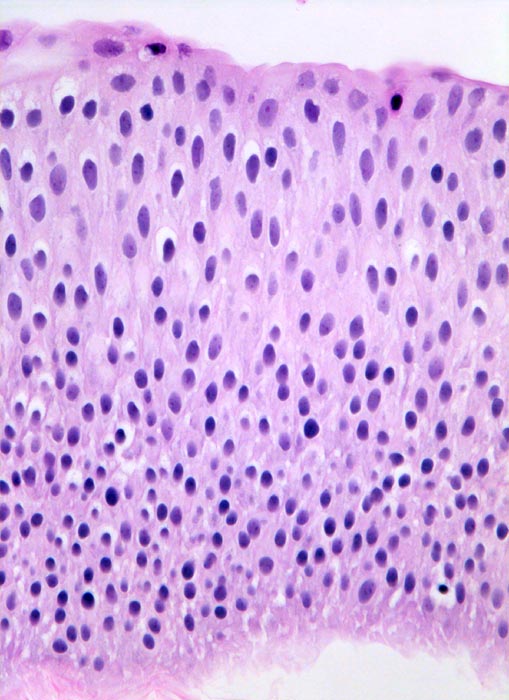

PathoPic – image database / PathoPic ID 5045 - Nicht invasives papilläres Urothelkarzinom pTa

Nicht invasives papilläres Urothelkarzinom pTa

Das bedeckende Urothel des papillären Tumors ist deutlich verbreitert. Zellatypien sind nicht vorhanden (histologischer Grad 1).

Normales Urothel umfasst in der Regel weniger als 7 Zellagen.